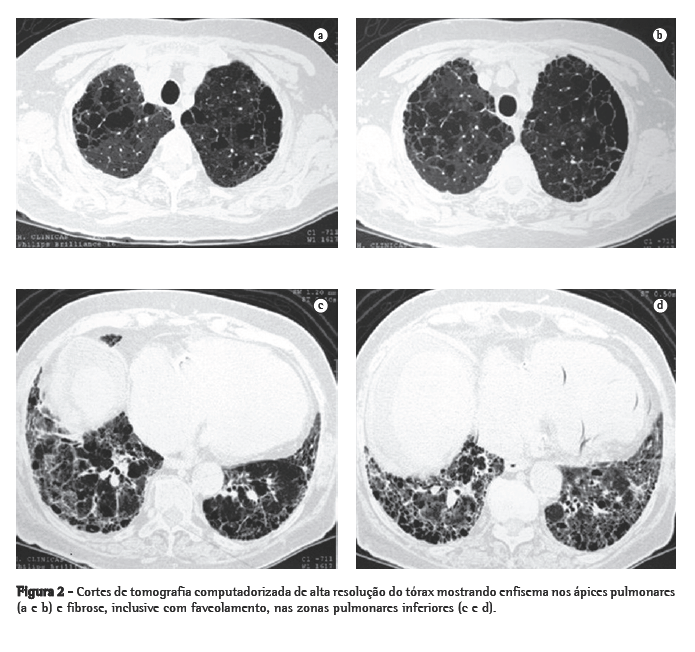

Todos os pacientes tinham achados compatíveis com enfisema e FPI na radiografia de tórax e na TCAR (Figuras 1 e 2). Áreas de radiotransparência em lobos superiores foram encontradas em todos os casos. Opacidades reticulares em bases pulmonares estavam presentes em 6 casos. Apenas 2 pacientes não apresentavam faveolamento. Em 4 casos evidenciaram-se áreas de atenuação em vidro despolido. Bronquiectasias de tração foram descritas em 3 dos 11 casos.